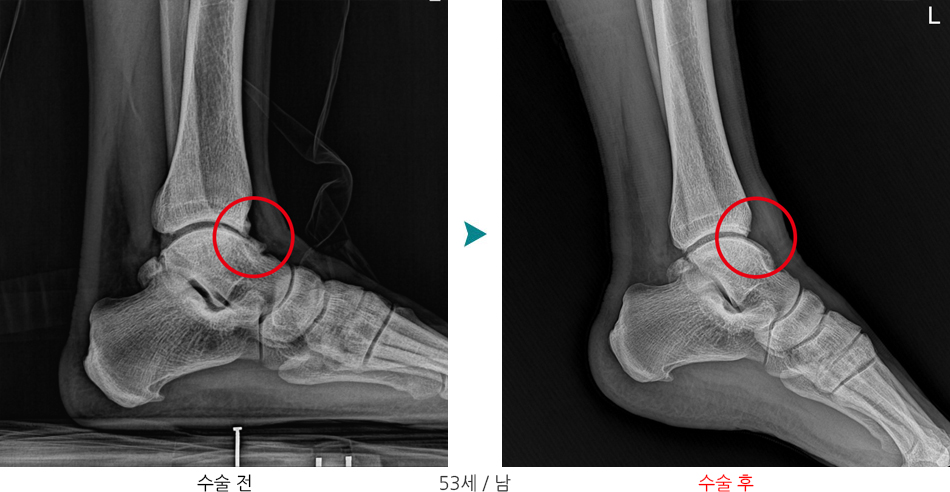

수술 치료

관절경 수술 - 전방 골극 제거 및 손상된 연부조직 절제 등

※ 발목 통증시 단순 염좌인 줄 알고 방치하면 만성화되어 수술까지 이어질 수 있으므로, 통증이 2주 이상 지속된다면 정확한 진단이 필요합니다.